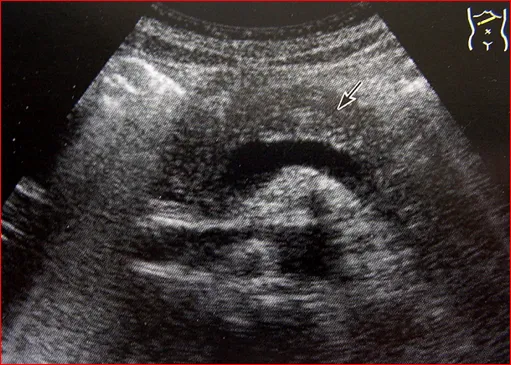

声像图

急性胰腺炎水肿型-增大

●急性胰腺炎出血坏死型-渗液